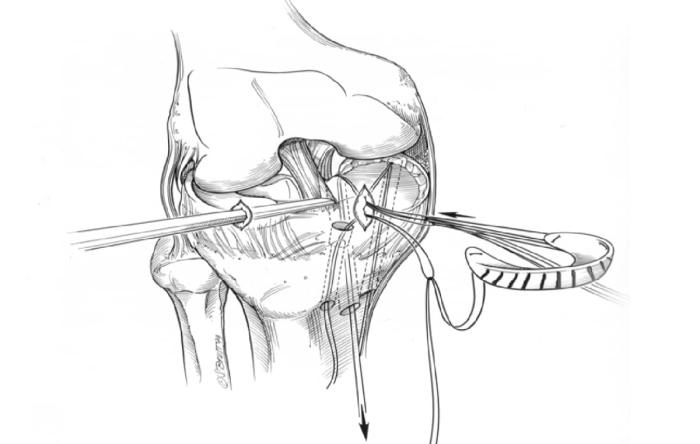

ACL surgery is performed more than 100,000 times...